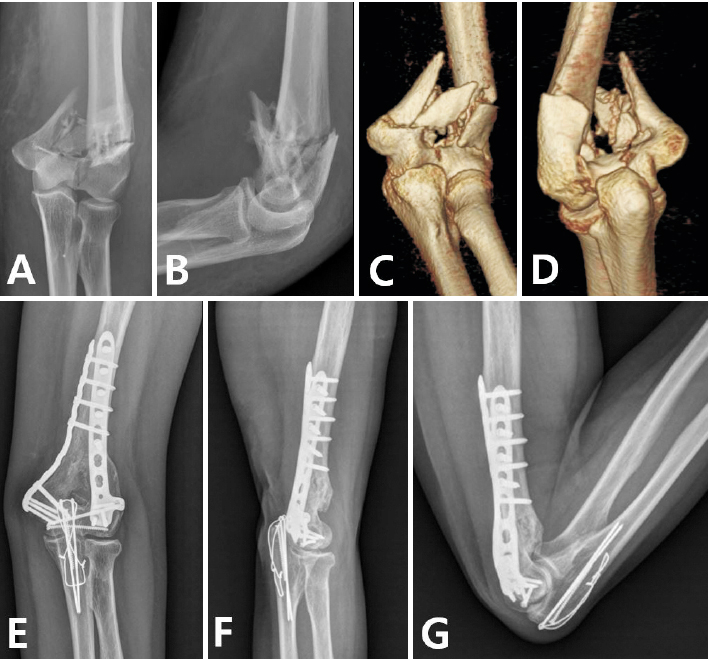

Fig. 5

Type 2 fracture. (A, B) Preoperative X-ray showed severe metaphyseal comminution. (C, D) Three-dimensional computed tomography. (E) Fracture was fixed by bridging plate. (F, G) Two years after operation, range of motion is nearly normal.